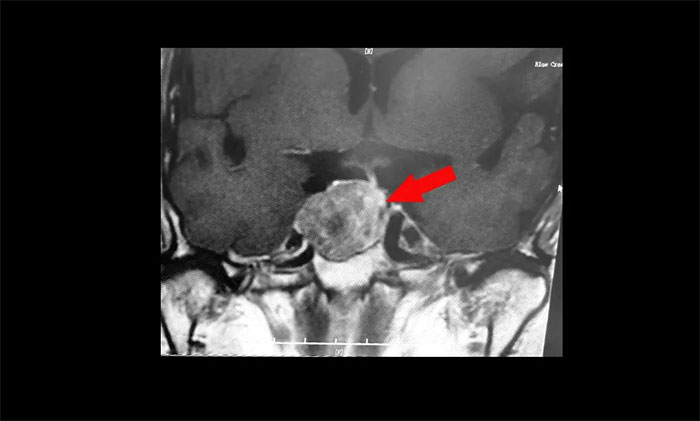

鞍區(qū)MRI平掃+增強(qiáng)顯示:蝶鞍顯著擴(kuò)大,鞍區(qū)見(jiàn)腫塊信號(hào),大小約29*19*24mm;垂體柄明顯縮短左偏;病變向鞍上生長(zhǎng),占據(jù)鞍上池,推移視交叉;向鞍旁生長(zhǎng),侵及右側(cè)海綿竇,右側(cè)海綿竇內(nèi)頸內(nèi)動(dòng)脈被推壓、包繞,右側(cè)頸內(nèi)動(dòng)脈海綿竇段較對(duì)側(cè)稍細(xì)。

▲ 腫瘤侵襲生長(zhǎng),包繞頸內(nèi)動(dòng)脈,knosp分級(jí)Ⅲ級(jí)